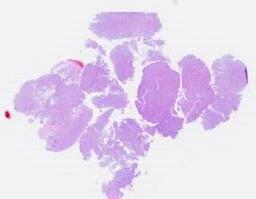

临床资料: 男,65岁,现病史:无咳嗽、咳痰、胸闷、发热等症状。无眼睑下垂、四肢乏力等特殊不适。影像结果:左肺尖段:混合磨玻璃结节,大小约32*29mm。前纵隔:软组织小结节影,大小约12*7mm。既往病史:平素体检,无特殊。